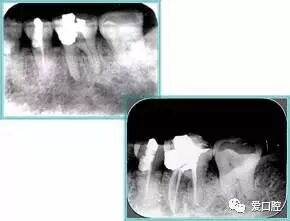

共有 4 张 X 线片,分别是术前、诊断丝 、主牙胶尖确认、术后。

( 1 )术前:术前 X 线片用来了解牙齿的大概情况。术前预期为多根牙时 X 线片应偏头拍摄。

( 2 )诊断丝:根据术前 X 线片进行开髓、根管的初步预备后,需要插入诊断丝,用来指示工作器械位置。常用 10 号或 15 号扩大器作为诊断丝插入牙髓腔。

( 3 )主牙胶尖确认:通过术前预期和诊断丝诊断,明确工作长度、牙根走向,进行根管预备。之后应进行主牙胶尖(中锉)确认,已明确根管是否适合充填。

( 4 )术后:观察治疗效果。